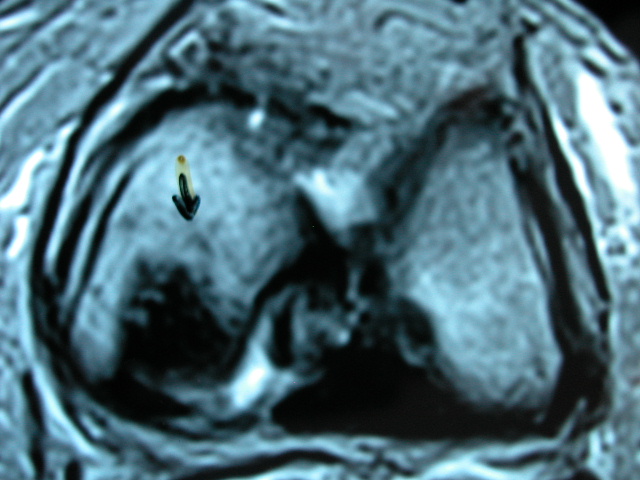

ACT Osteonecrosis de rodilla. RM.